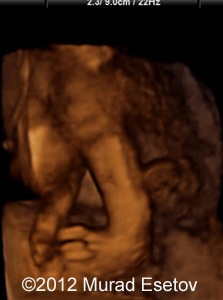

Image 2 show a 3D rendering of the lumbar spine showing in the midline projecting the spur (asterisk) dividing the spinal canal into two parts (arrow)

Image-2